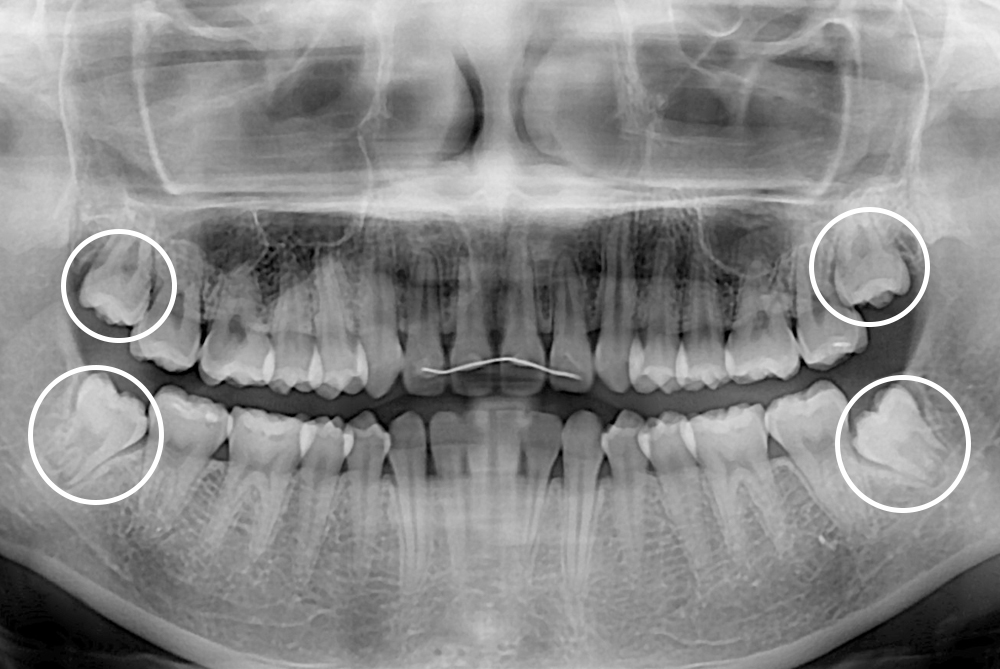

[사랑니] 매복 사랑니 발치

치료후 : 2017-10-07

세종치과는 구강악안면외과학 박사이신 원장님이 발치하는 치과입니다.